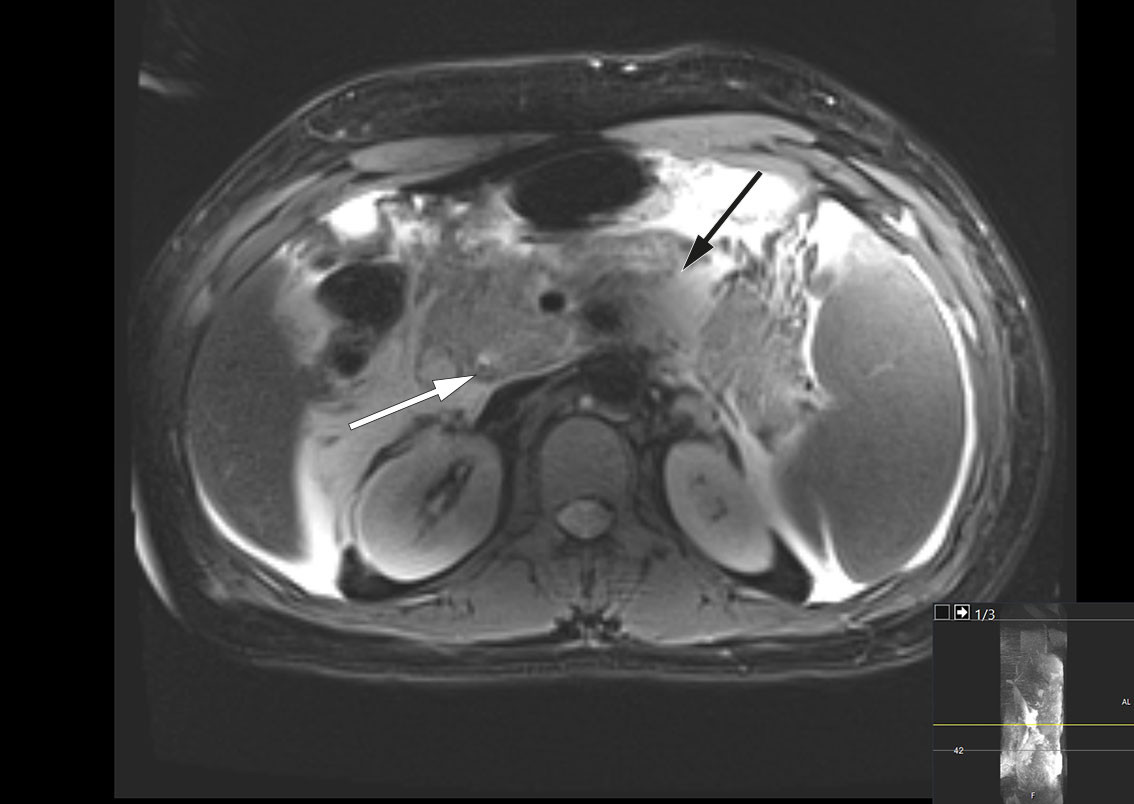

The patient gradually improved and was discharged after 18 days. Three days later, however, he was readmitted due to increasing pain and dyspnoea. A CT scan revealed encapsulation of peripancreatic necrotic fluid collections with partial compression of the portal and splenic veins. There was no evidence of cholestasis, and a slight reduction in free fluid was seen in the abdominal cavity. Blood tests showed signs of inflammation, and oral antibiotic treatment was initiated in the form of trimethoprim/sulfamethoxazole 160 mg/800 mg, twice daily, along with metronidazole 400 mg three times daily, due to suspected secondary infection of necrosis. The patient was discharged home without further antibiotic treatment eight days after the second admission. Endoscopic transgastric drainage of encapsulated necrotic fluid collections, known as walled-off necrosis (WON), was planned for the following week, due to compression of the portal and splenic veins.

The following day, the patient was febrile with a temperature of 38.5°C but was stable on room air. The encapsulated necrosis was treated by inserting a Hot AXIOS lumen-apposing metal stent (LAMS), a system developed for endoscopic ultrasound-guided drainage of encapsulated necrosis via the stomach. A feeding tube was placed in the small intestine, and nutritional supplementation was initiated. Over the following days, the patient's clinical and biochemical status fluctuated. Broad-spectrum intravenous antibiotics were initiated in the form of meropenem 1 g three times daily due to an increase in CRP to 148 mg/L. In addition, a fall in haemoglobin to 6.9 g/dL led to the decision to transfuse the patient with three units of packed red cells. A CT scan, however, showed a significant reduction in the size of the encapsulated necrosis after placement of the stent, and showed the blood vessels to no longer be compressed (Figure 3). The patient underwent necrosectomy via gastroscopy, with removal of large amounts of dead tissue. Over the next few days, the patient was gradually mobilised, with accompanying improvements in respiration and good diuresis supported by loop diuretics. Two sets of blood cultures were sterile, while Staphylococcus epidermidis was detected in the urine but was of uncertain clinical significance. The epidural catheter was removed, and opioids were tapered in accordance with the patient's increasing mobility. The patient was then transferred to the gastroenterological surgery ward on day 10 of his third admission.